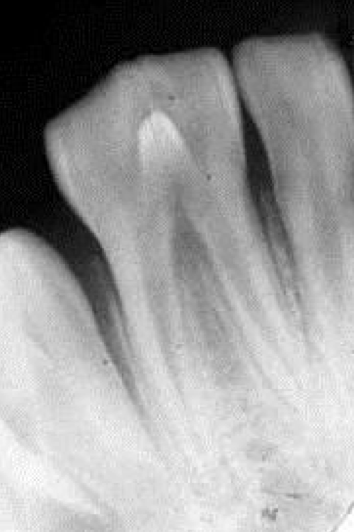

What would present with this kind of radiopaque spot within this tooth?

Dens-in-dente